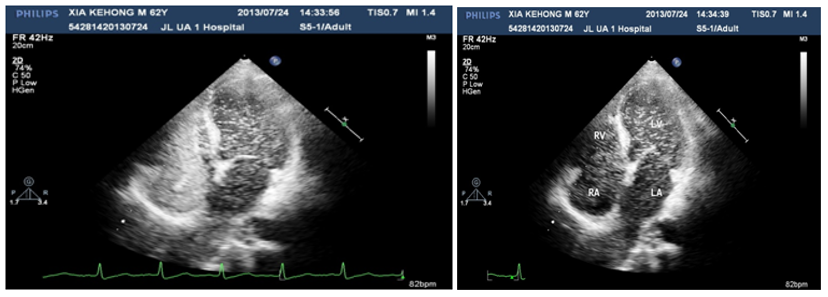

Figure 2&3 The density of micro-bubbles was the same in the left and right cardiac chambers even after 10 cardiac cycles.

Figure 4 When the injection was stopped, there were micro-bubbles in the left cardiac chambers meanwhile none in the right cardiac chambers.

A 60years old male, known case of diabetes mellitus, hypertension and alcoholic hepatic cirrhosis had exercise induced chest discomfot, shortness of breath, fatigue and lips cyanosis half a year ago, which relieved at rest. But later he became serious for one week and visited our department for further management. He had no cough, fever, dizziness, headache or bleeding history from any site. He had pituitary adenoma, which was surgically removed 6years ago. He denies history of chronic infections such as tuberculosis or actinomycosis or family history of hereditary hemorrhagic telangiectasis (HHT). Physical examination revealed cyanosis of the face and lips, clubbing, numerous spider naevi on neck, chest and palm and no telangiectasia on mucosa or fundi. His blood pressure was 130/80mmHg, heart rate was 76beats/min and resting oxygen saturation was 66% in room air. A grade 1/6 soft systolic murmur was heard on the upper left sternal border and clear lungs sound. There were no bruits. The hemoglobin was 11.5gm/dL and the hematocrite was 35.5gm/dL. Arterial blood gas analysis showed Pao2 64mmHg on room air and after 100% of oxygen 74mmHg with Paco2 41mmHg and PH-7.35. Chest radiography and electrocardiogram did not show any abnormalities. Pulmonary function test showed alveolar dispersion function severely reduced. Transthoracic echocardiography showed normal findings (No PFO/ASD/VSD/PDA detected). We performed contrast echocardiography using agitated saline. A delayed appearance of a substantial amount of micro-bubbles in the left atrium greater than three cardiac cycles after appearance in the right atrium and ventricle (Figure 1) which was suggestive of pulmonary arteriovenous fistula. The delayed appearance and a large amount of micro-bubbles in the left atrium preclude the intracardiac shunting resulting from a patent foramen ovale (PFO) or arterial septal defect (ASD). Interestingly, the density of micro-bubbles was the same in the left and right cardiac chamber even after 10 cardiac cycles (Figure 2 & 3) and when the injection stopped, there were micro-bubbles in the left cardiac chambers meanwhile none in the right cardiac chambers (Figure 4). Because the hepatic function of the patient was in compensatory period, we gave him oxygen-inhalation and beta-blockers in order to decrease the oxygen demands and to lower the portal vein pressure. Moreover, he was advised to avoid sudden standing. The cyanosis improved, and the patient was discharged from the hospital and on regular follow-up. The patient was advised for pulmonary angiography but refused.